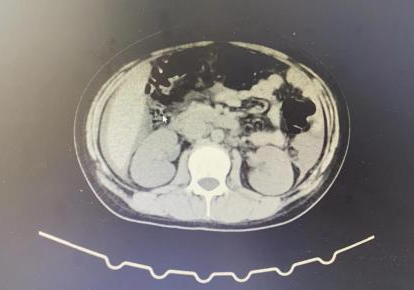

近日,贵阳市妇幼保健院儿童重症医学科(PICU)收治一位外院转诊的患者。该患者年仅13岁,咳嗽、腹痛5天。该院PICU医师立即进行了相关查体及检查,发现该患者双肺呼吸音粗,双下肢呈非凹陷性水肿。同时辅助检查提示双肺散在絮状密影,双肺胸腔少量积液,伴心脏明显增大,心包大量积液。大量的心包积液导致患者开始出现呼吸困难,剑突下疼痛等症状,救治刻不容缓。

根据患者病史及中心实验室检测报告在PICU、心脏外科、药剂科联合会诊后,确诊该患者为并殖吸虫感染者,及时优化治疗方案,予以吡喹酮口服治疗。在吡喹酮仅治疗2天,患者心包积液较前明显减少,逐渐监测心包闭式引流管未见液体引出,复查CT提示患者明显好转,已达临床出院标准。